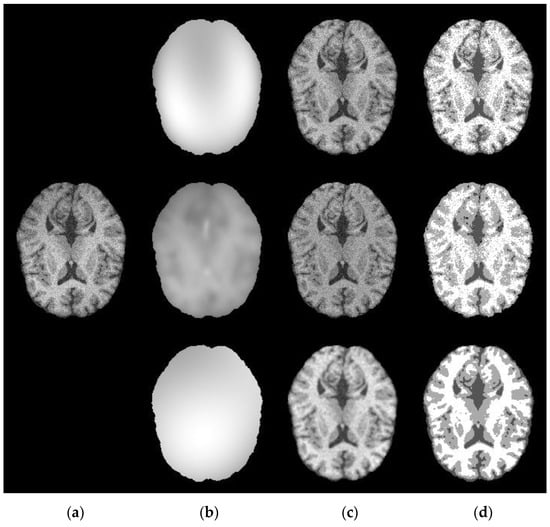

4.2. Capability of Estimating the Bias Field